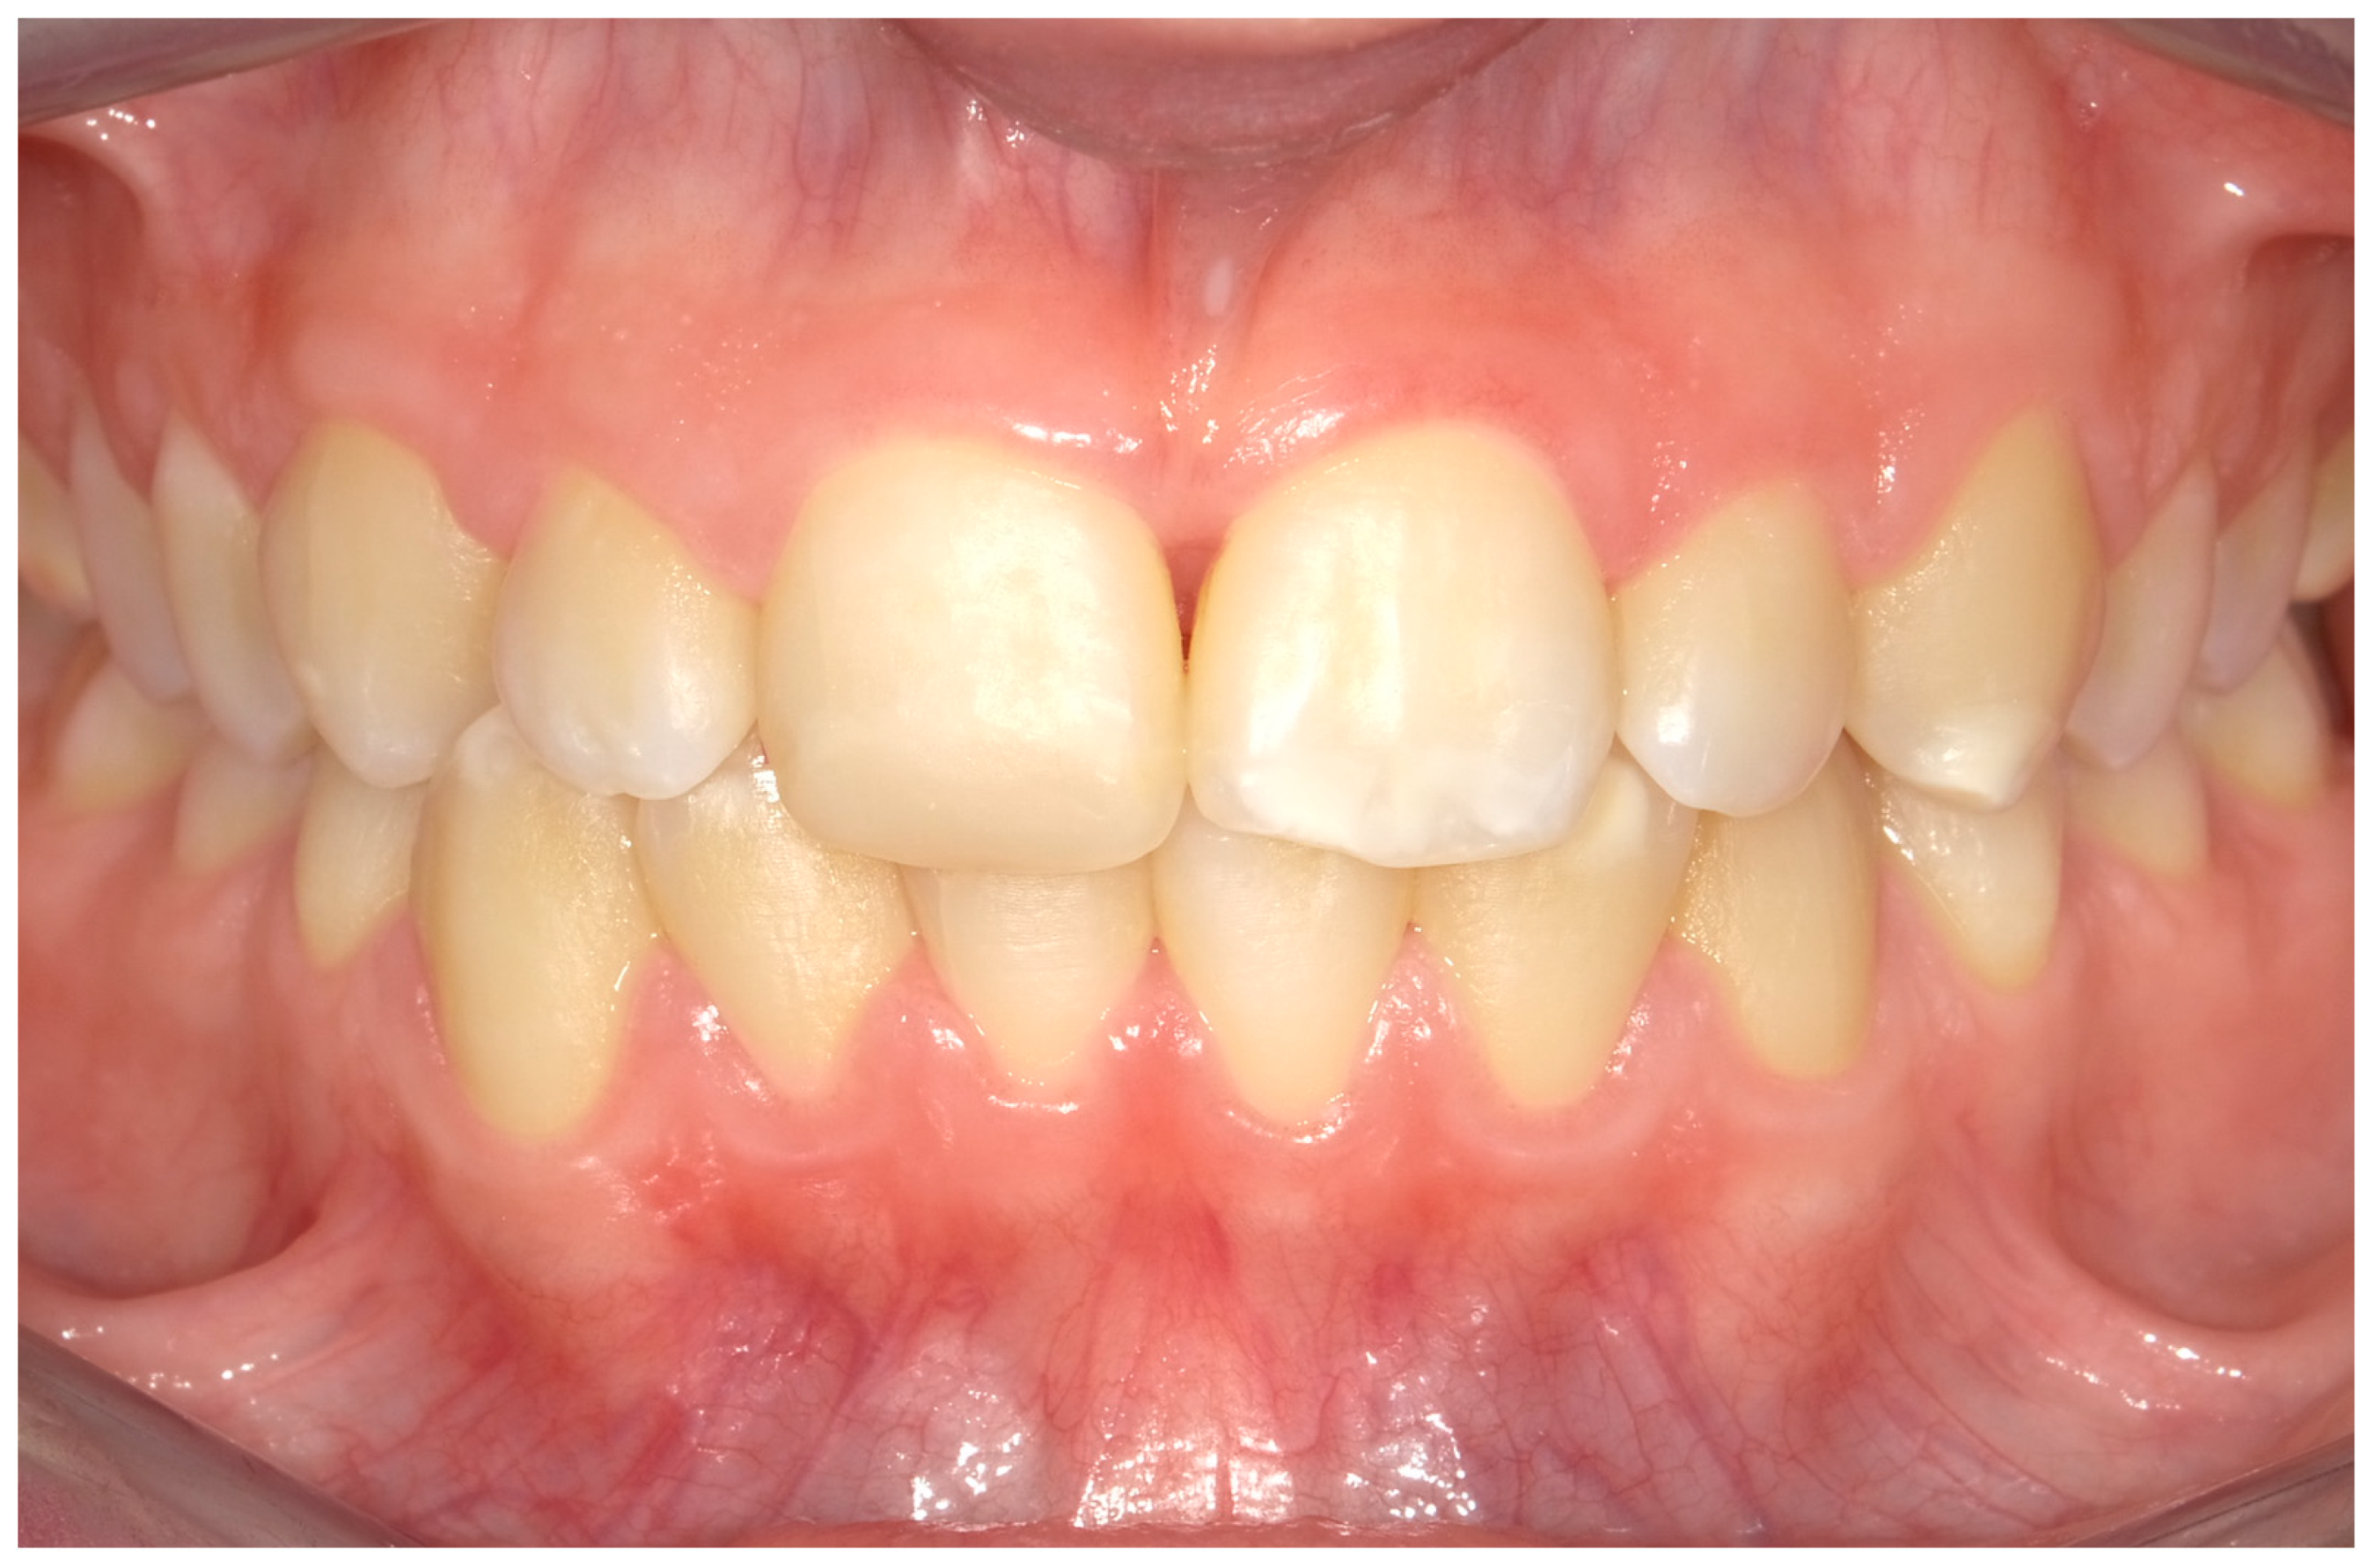

4.1. Case 1